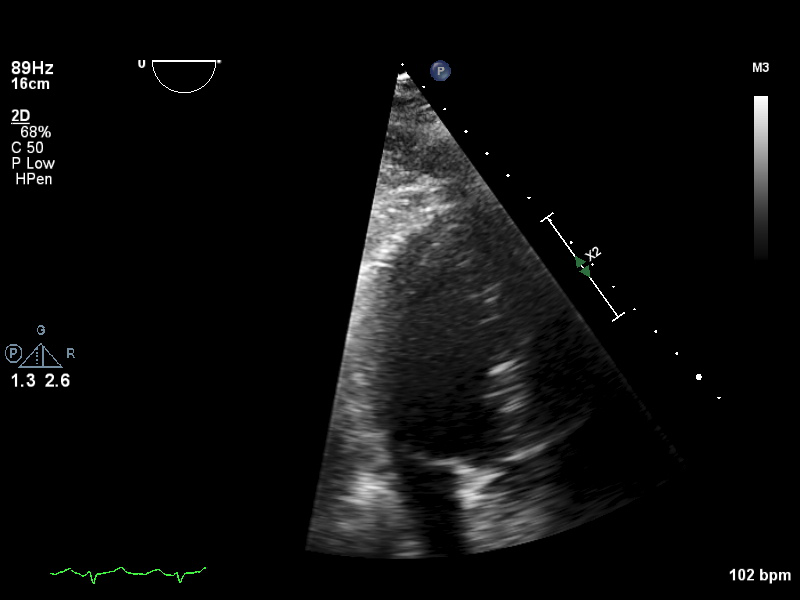

ImageView NameDescription

apex apex Any apical window whose depth is insufficient to reach the mitral ring